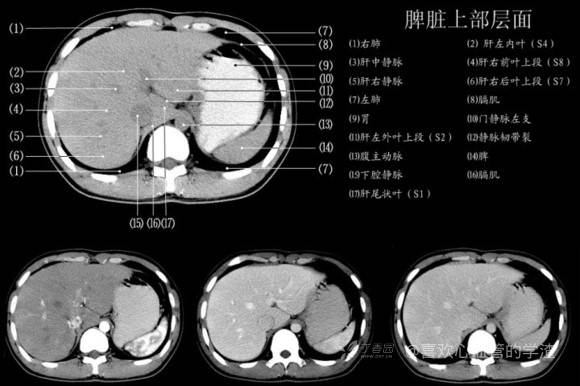

其实你离掌握上腹部 CT 影像只有一套高清实用图谱的距离,下面把我最喜欢的这本图谱分享给大家,为了方便阅读,我加了中文标识。后面附赠几张血管相对位置解剖关系图片,帮助大家理解(文中多图,建议在 wifi 环境下查看)。